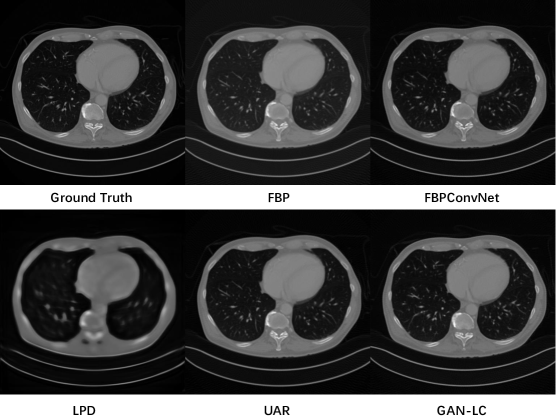

To illustrate the reconstruction performances more clearly, we also show the reconstruction results for testing images in Figure 3. We can see that our network can reconstruct the CT image with higher quality. Due to the space limit, the experimental results of different views and more visualized results are placed in our supplementary material.